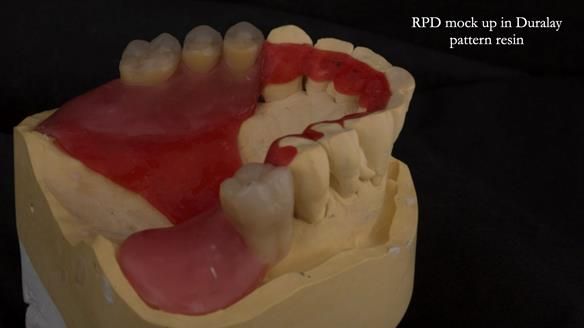

Instead, we made a Scandinavian-style, metal-based lower RPD.

It was made promptly, then relined gradually over the following year

to optimise fit, comfort, and support.

It’s worth saying that the lower denture in this case was made in the early days of Rowan and me using the Scandinavian approach. Rowan cast the metalwork himself for this denture.

Looking back, we would make this denture more hygienic now. The design and finish would be more refined and delicate, particularly when compared with the upper metalwork, which was made later using Chris Hesketh’s chrome work. I will discuss this in detail at the study club.

That said, the lower denture worked beautifully. It did exactly what it was meant to do, even though, by today’s standards, it looks a little agricultural.